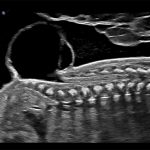

Imagini clinice:

Aplicatii: